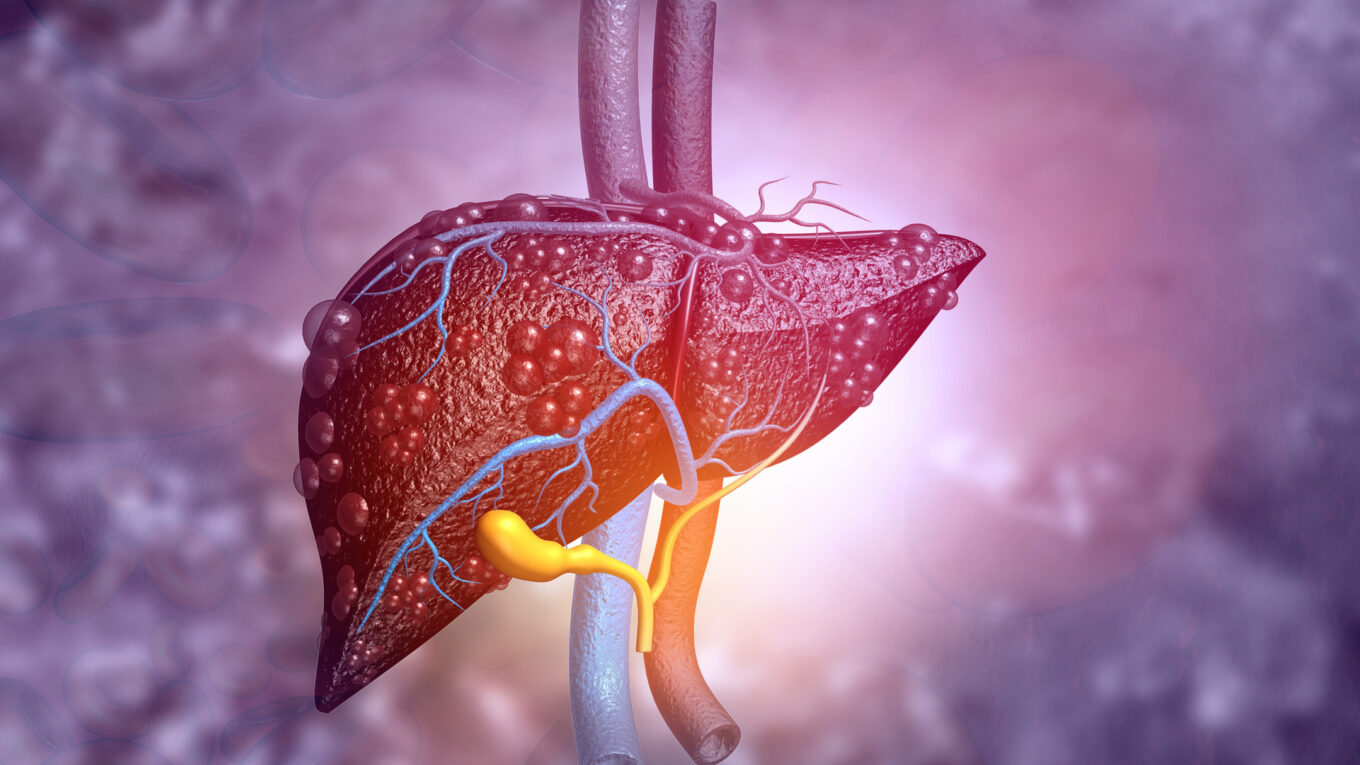

An international clinical trial involving Birmingham Professor Phil Newsome identified a promising target for patients with non-alcoholic steatohepatitis (NASH), as reported in a paper published yesterday in Nature Communications. The research team demonstrated that an oral inhibitor of amine oxidase copper-containing 3 (AOC3), a protein involved in liver inflammation – which can lead to fibrosis, cirrhosis and liver cancer – successfully suppressed this protein, as well as reducing liver injury.

The study, which tested an oral inhibitor produced by pharmaceutical company Boehringer Ingelheim, builds on the University of Birmingham’s long-standing work on AOC3 inhibition led by David Adams and Chris Weston, and validates this protein as a promising target to reduce liver inflammation, with the potential for subsequent beneficial effects on fibrosis in patients with NASH. The current standard of care for NASH is limited to lifestyle interventions, such as weight loss and exercise, which reduce inflammation and, indirectly, fibrosis. Building on this trial, pharmaceutical research company Pharmaxis will explore the potential to develop a safe and effective pharmacological treatment for NASH patients.